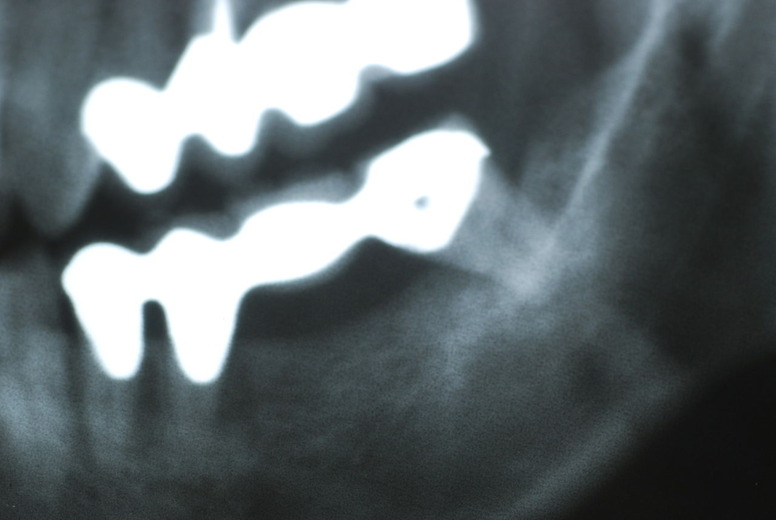

レントゲンでは小さいですが、こう言う虫歯が一番怖いのです。

治療の成功率は極めて悪くすぐ再発しやすいのです。

隣の14歳大臼歯がひどい虫歯になり治療不可能になりつつある状態のレントゲン